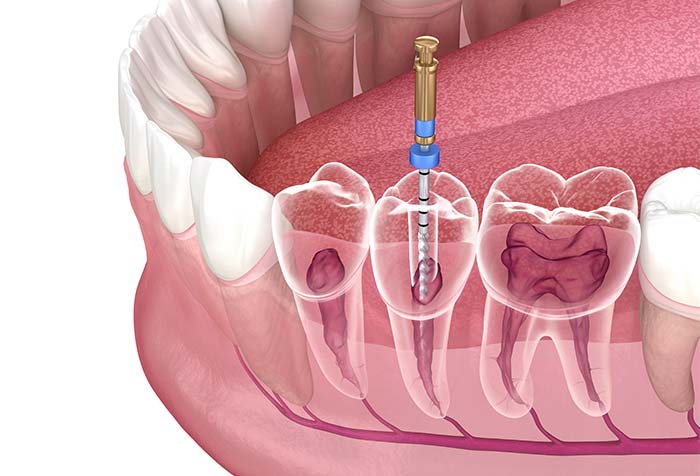

根管治療とは、歯の根の部分を治す治療です。むし歯が進行すると感染が歯の根まで及び、炎症や強い痛みを引き起こします。その場合、感染した組織を取り除き、根管の内部を殺菌して薬を詰め、密閉することで無菌に近い状態にします。こうした処置により、歯を抜かずに残せることもあります。なお、難しい症例については根管治療を専門とする歯科医師が在籍している歯科医院をご紹介しています。